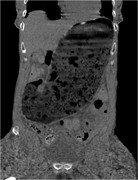

Retroperitoneal calcifying fibrous tumor mimicking an adrenal tumor

Erica C. Prochaska and others

Journal of Surgical Case Reports, Volume 2016, Issue 6, June 2016, rjw049, https://doi.org/10.1093/jscr/rjw049